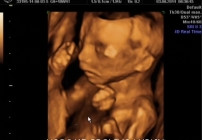

BADANIE USG 3/4D umożliwa dokładny wgląd w rozwój płodu, pozwala na podglądnięcie dziecka w sposób niemalże identyczny z jego aktualnym wyglądem.

W trakcie trwania badania obraz rejestrowany jest na płycie DVD, tak aby każdy przyszły rodzic mógł ponownie odtworzyć badanie w domowym zaciszu. Podczas badania płodu USG 3/4D istnieje również możliwość wydruku zdjęć w formacie kartki pocztowej(148 × 100 mm). Doskonałą jakość, którą charakteryzują się wykonywane przez nas odbitki cyfrowe uzyskujemy dzięki używaniu wyłącznie markowych papierów fotograficznych.